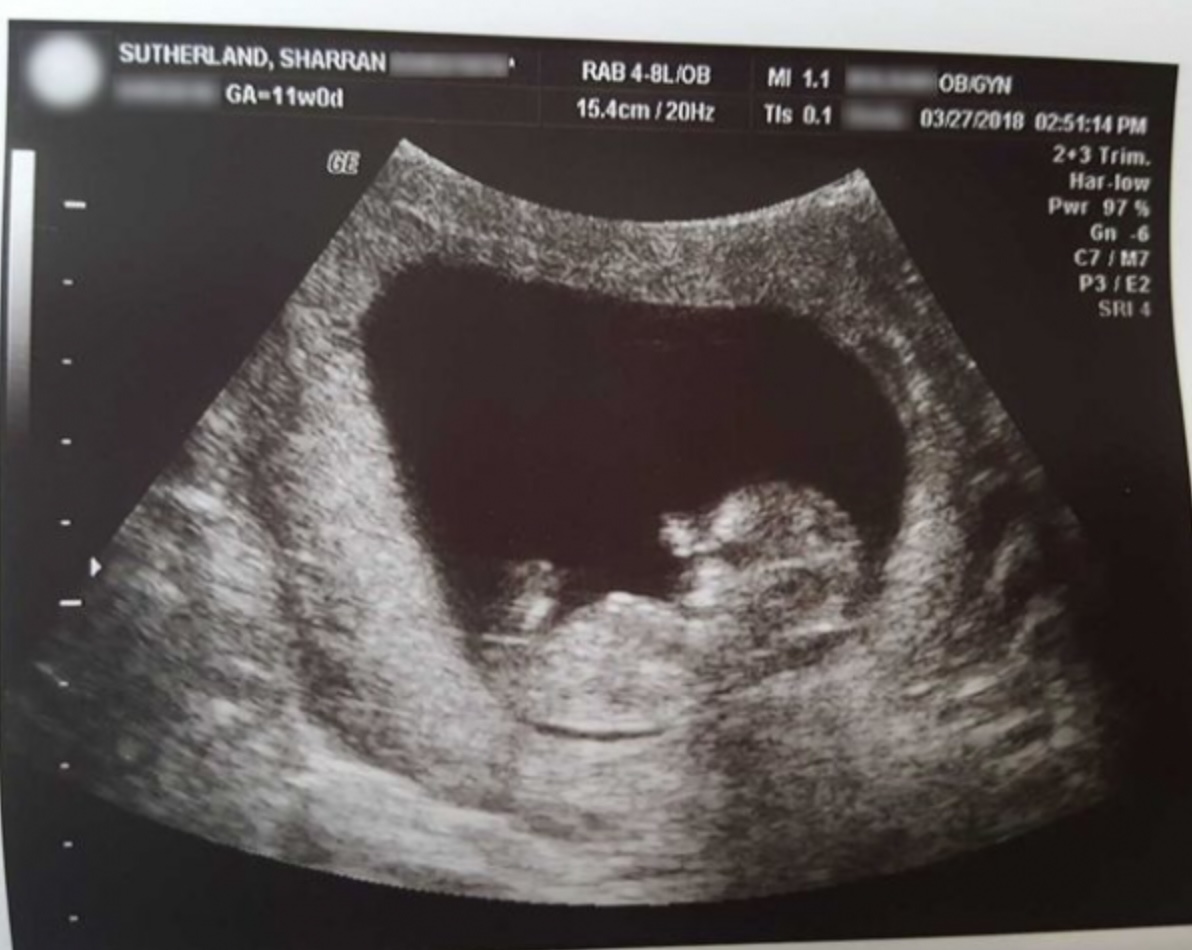

【令人心痛】40歲準媽媽懷孕14周胎死腹中 堅拒讓醫生當BB醫療廢物丟棄:胎兒再小仍是生命

每位準媽媽都希望自己能誕下健健康康的寶寶,然而在美國有一名40歲的孕婦在懷孕14周產檢時,被醫生告知胎兒的心跳停止了,更建議她做引產手術,把死胎當作醫療廢物處理。不過該名準媽媽認為自己的孩子並不是醫療廢物,堅持自然分娩將已逝的寶寶生下來,並把胎兒帶回家安葬。隨後該名媽媽拍下兒子的照片分享至社交平台,不少網民看了照片後都大為感動,表示胎兒再小仍是生命,形容她做了世上最偉大的事!

胎兒在14週時停止心跳

40歲的莎倫(Sharran Sutherland)與35歲丈夫麥克爾(Michael Sutherland)居住在密蘇里州,兩人好不容易懷了男寶寶,正期盼孩子在腹中健康成長,不料卻在14周產檢時得知噩耗。醫生發現胎兒失去呼吸和心跳,建議莎倫做引產手術取出胎兒,更稱因為胎兒要足20周才可合法定義為嬰兒,否則便需當作醫療廢物處理。

莎倫聽後感到非常憤怒,「我不能相信醫生把他當作醫療廢物。」莎倫不忍心寶寶在手術過程被剪成碎片,取出後淪為「醫療棄物」,於是堅持選擇在預產期前173天自然分娩,誕下僅長約10厘米、重26克的兒子,並為兒子取名為米朗(Miran Sutherland)。